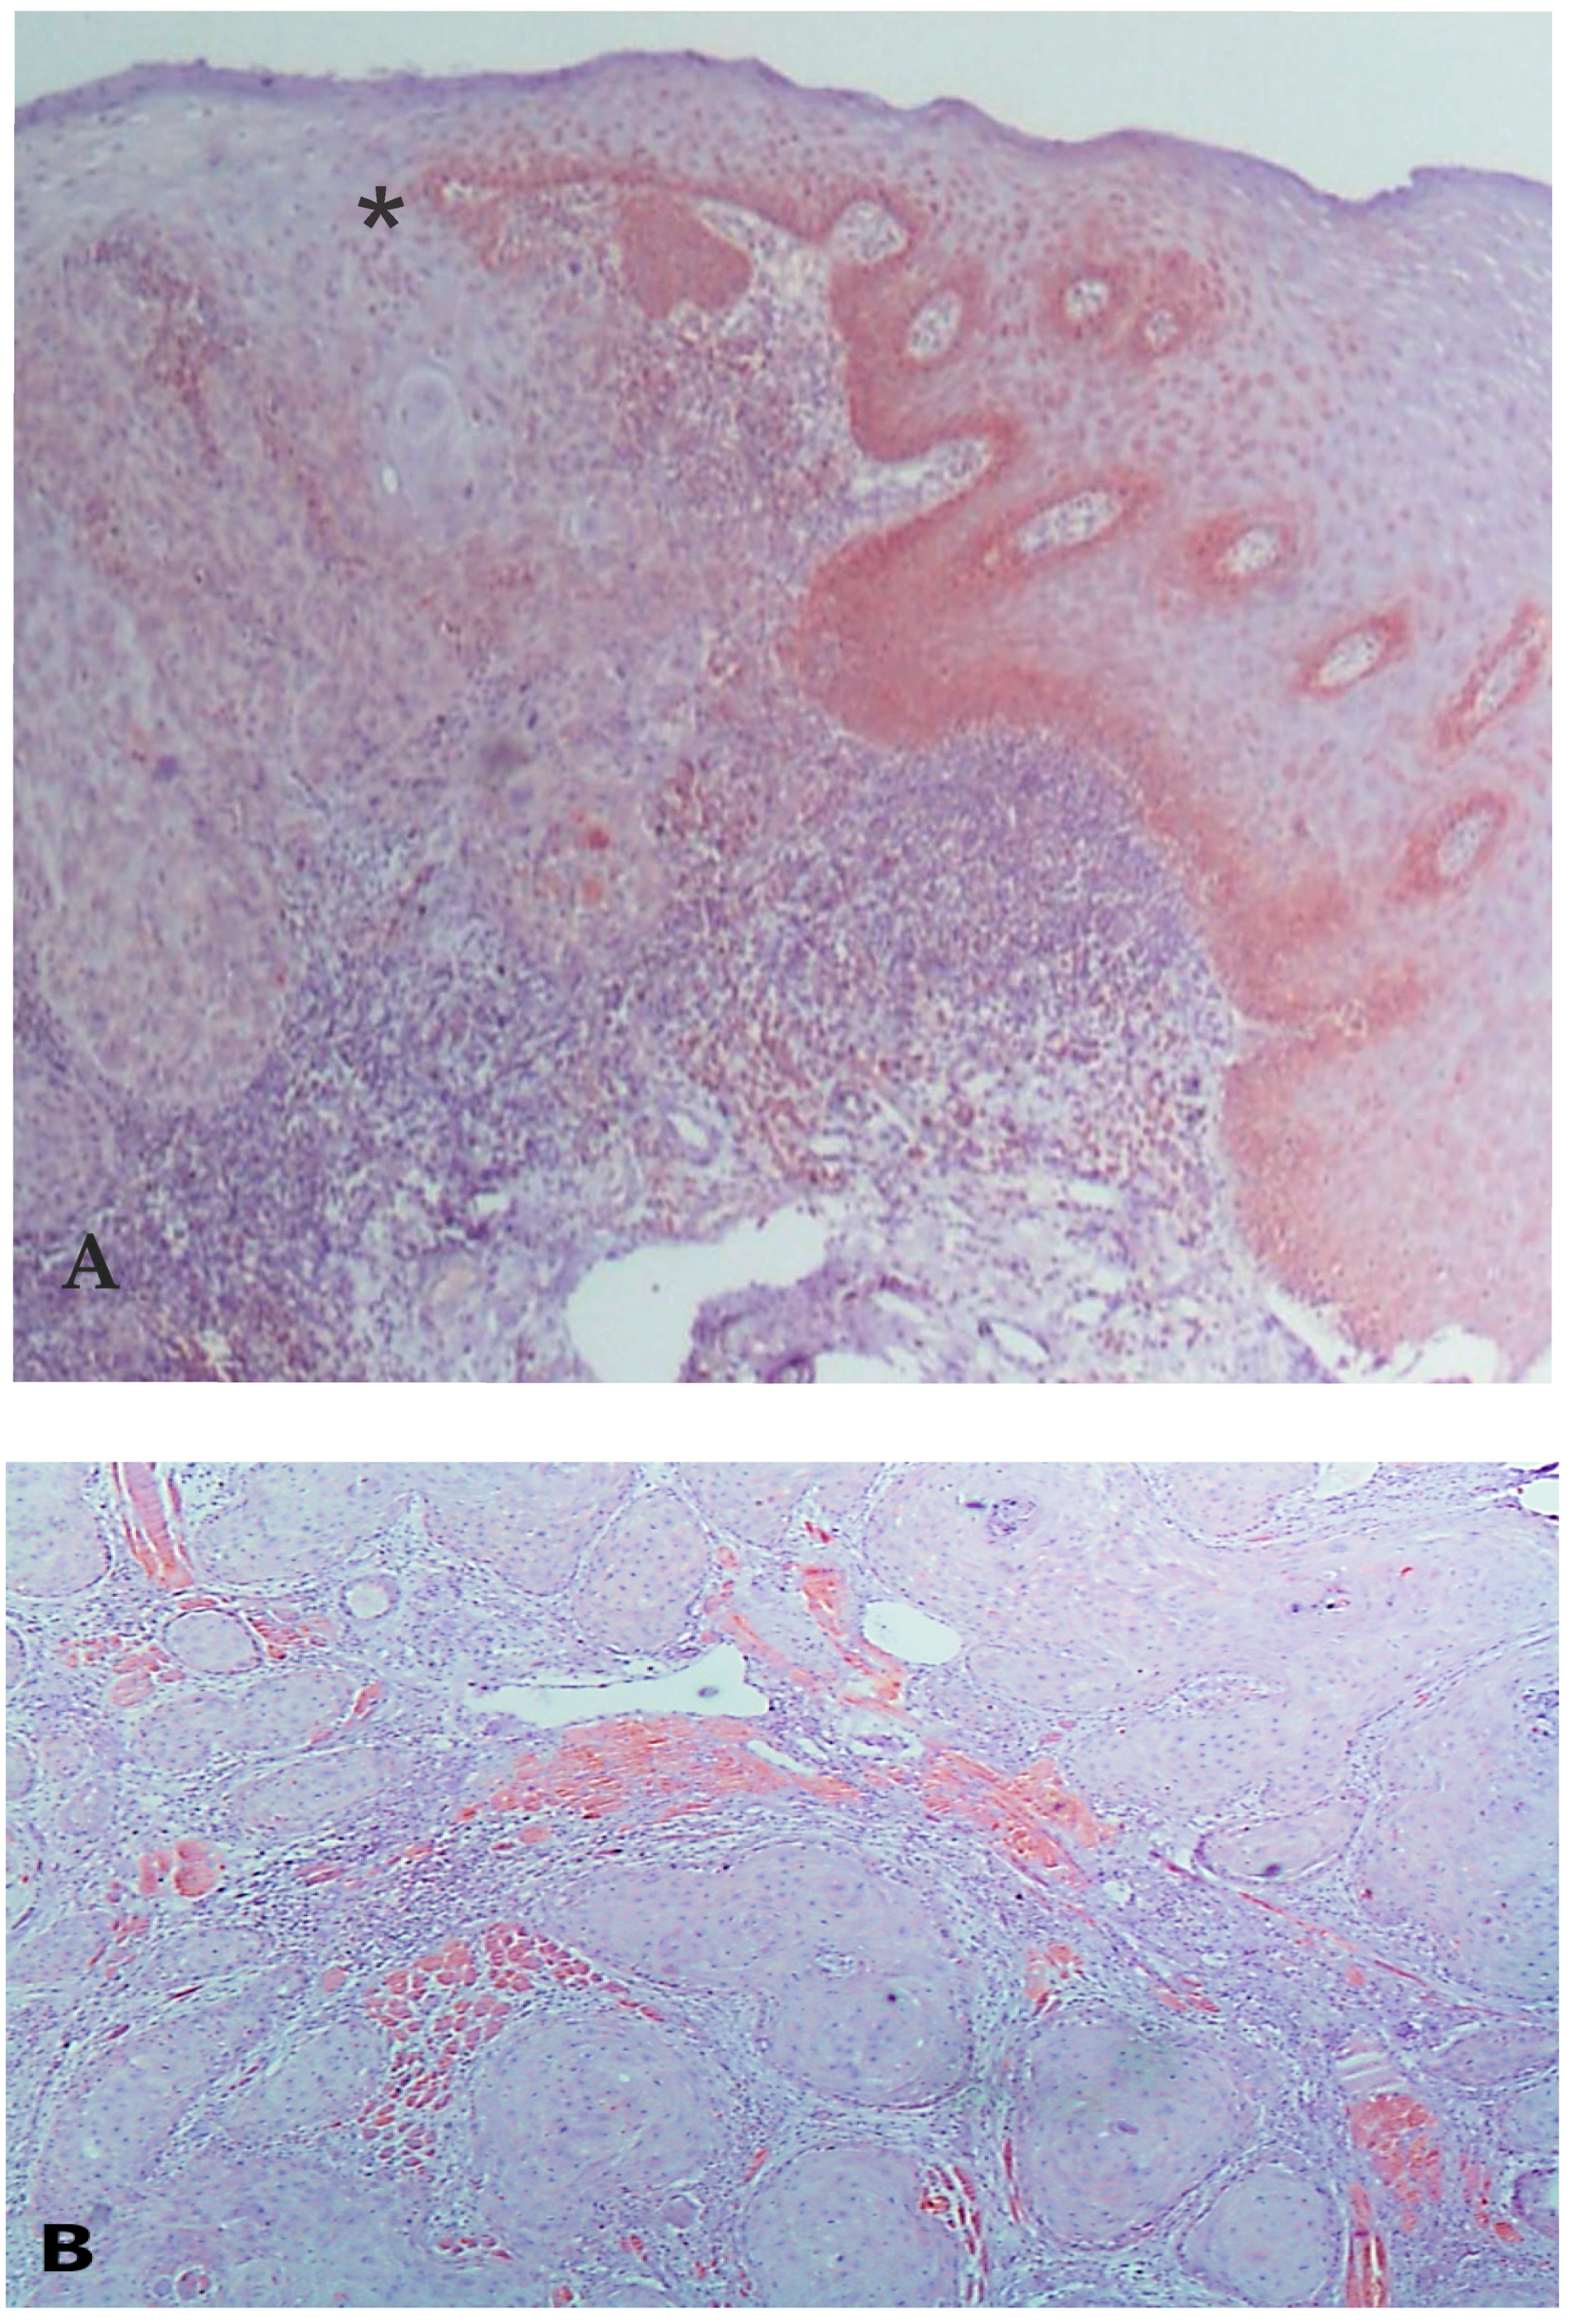

2.2. Immunohistochemistry and Immunomorphometry

3. Results

3.3. VDAC1 Expression